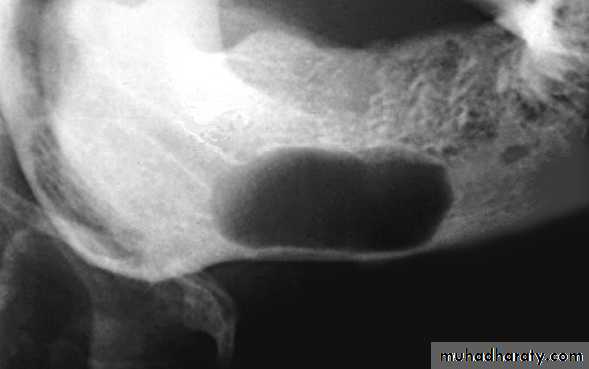

The probability of cartilaginous lesions and osteochondromas occurring is greater in the condylar region.

Shape

1-Circular or fluid-filled shape, is characteristic of a cyst.2-Scalloped shape is a series of contiguous arcs or semicircles that may reflect the mechanism of growth. This shape may be seen in cysts (e.g., keratocystic odontogenic tumors), cyst like lesions (e.g., simple bone cysts), and some tumors. Occasionally, a lesion with a scalloped periphery is referred to as multilocular.

The presence of reactive bone at the periphery of a lesion whether corticated or sclerotic usually signifies slow benign growth and ability to stimulate osteoblastic activity in the surrounding bone